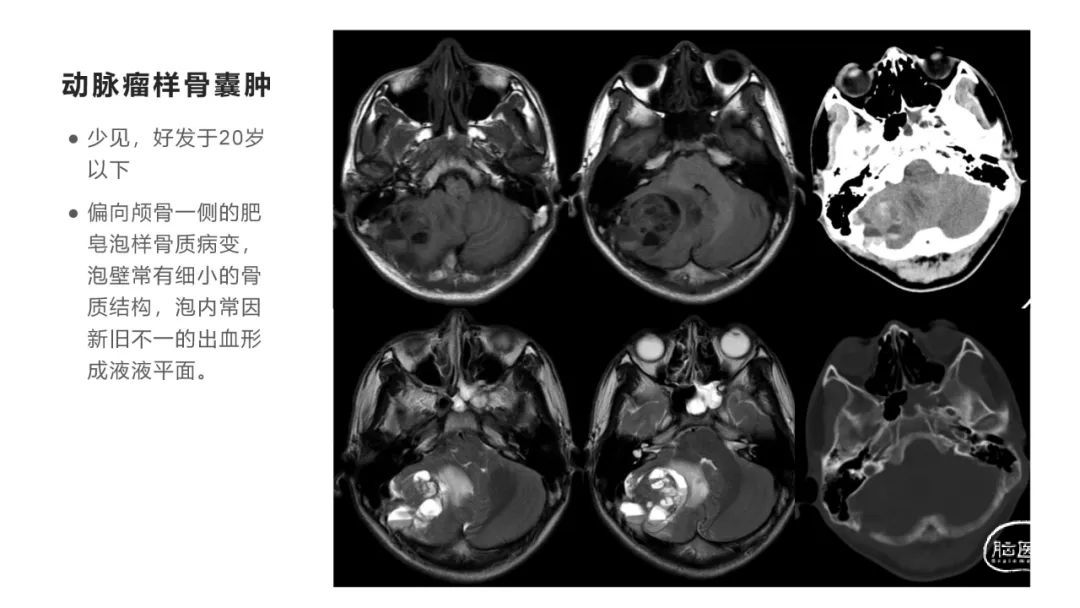

颅脑影像诊断基础知识讲座:颅骨病变